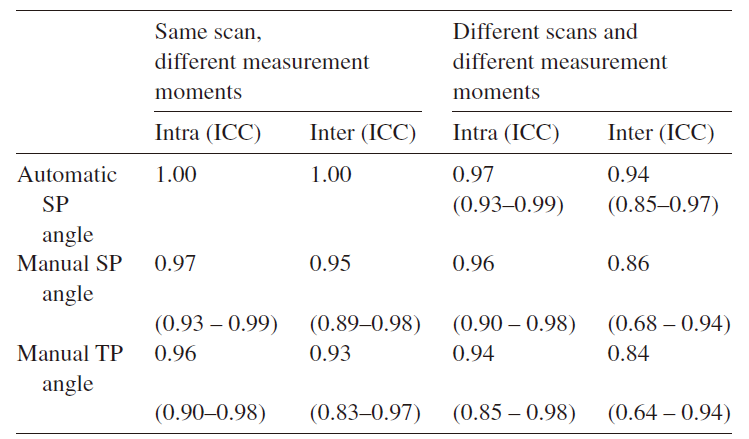

研究团队使用Windows的SPSS 22.0软件进行数据分析,以组内相关系数(ICC)评定可靠性,ICC值介于0~1之间,0.8~1表示非常可靠,0.6~0.79表示可靠性中等,小于等于0.6表示可靠性存疑。

实验中,自动棘突角、手动棘突角和手动横突角这三个冠状面角度的ICC值介于0.84~1之间,数据证明超声测量脊柱侧弯角度的结果可靠性优秀,与传统Cobb角的可靠性(0.83–0.99)相符。